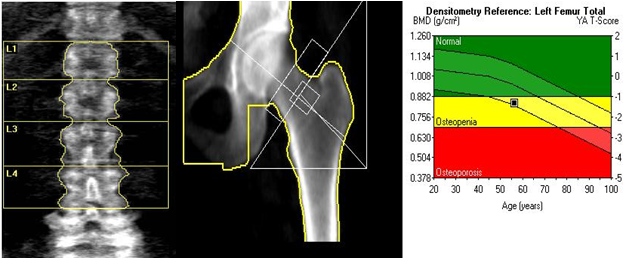

- 골절 위험 조기 예측: DXA(이중에너지 X선 흡수계측)로 요추·대퇴부 골밀도를 측정해 T-score를 얻습니다.

검사 결과 읽는 법(기본)

- T-score ≥ –1.0 : 정상

- –2.5 < T-score < –1.0 : 골감소증(생활습관 개선·칼슘 1,200 mg 권장)

- T-score ≤ –2.5 : 골다공증(약물·정기 추적검사 필요)